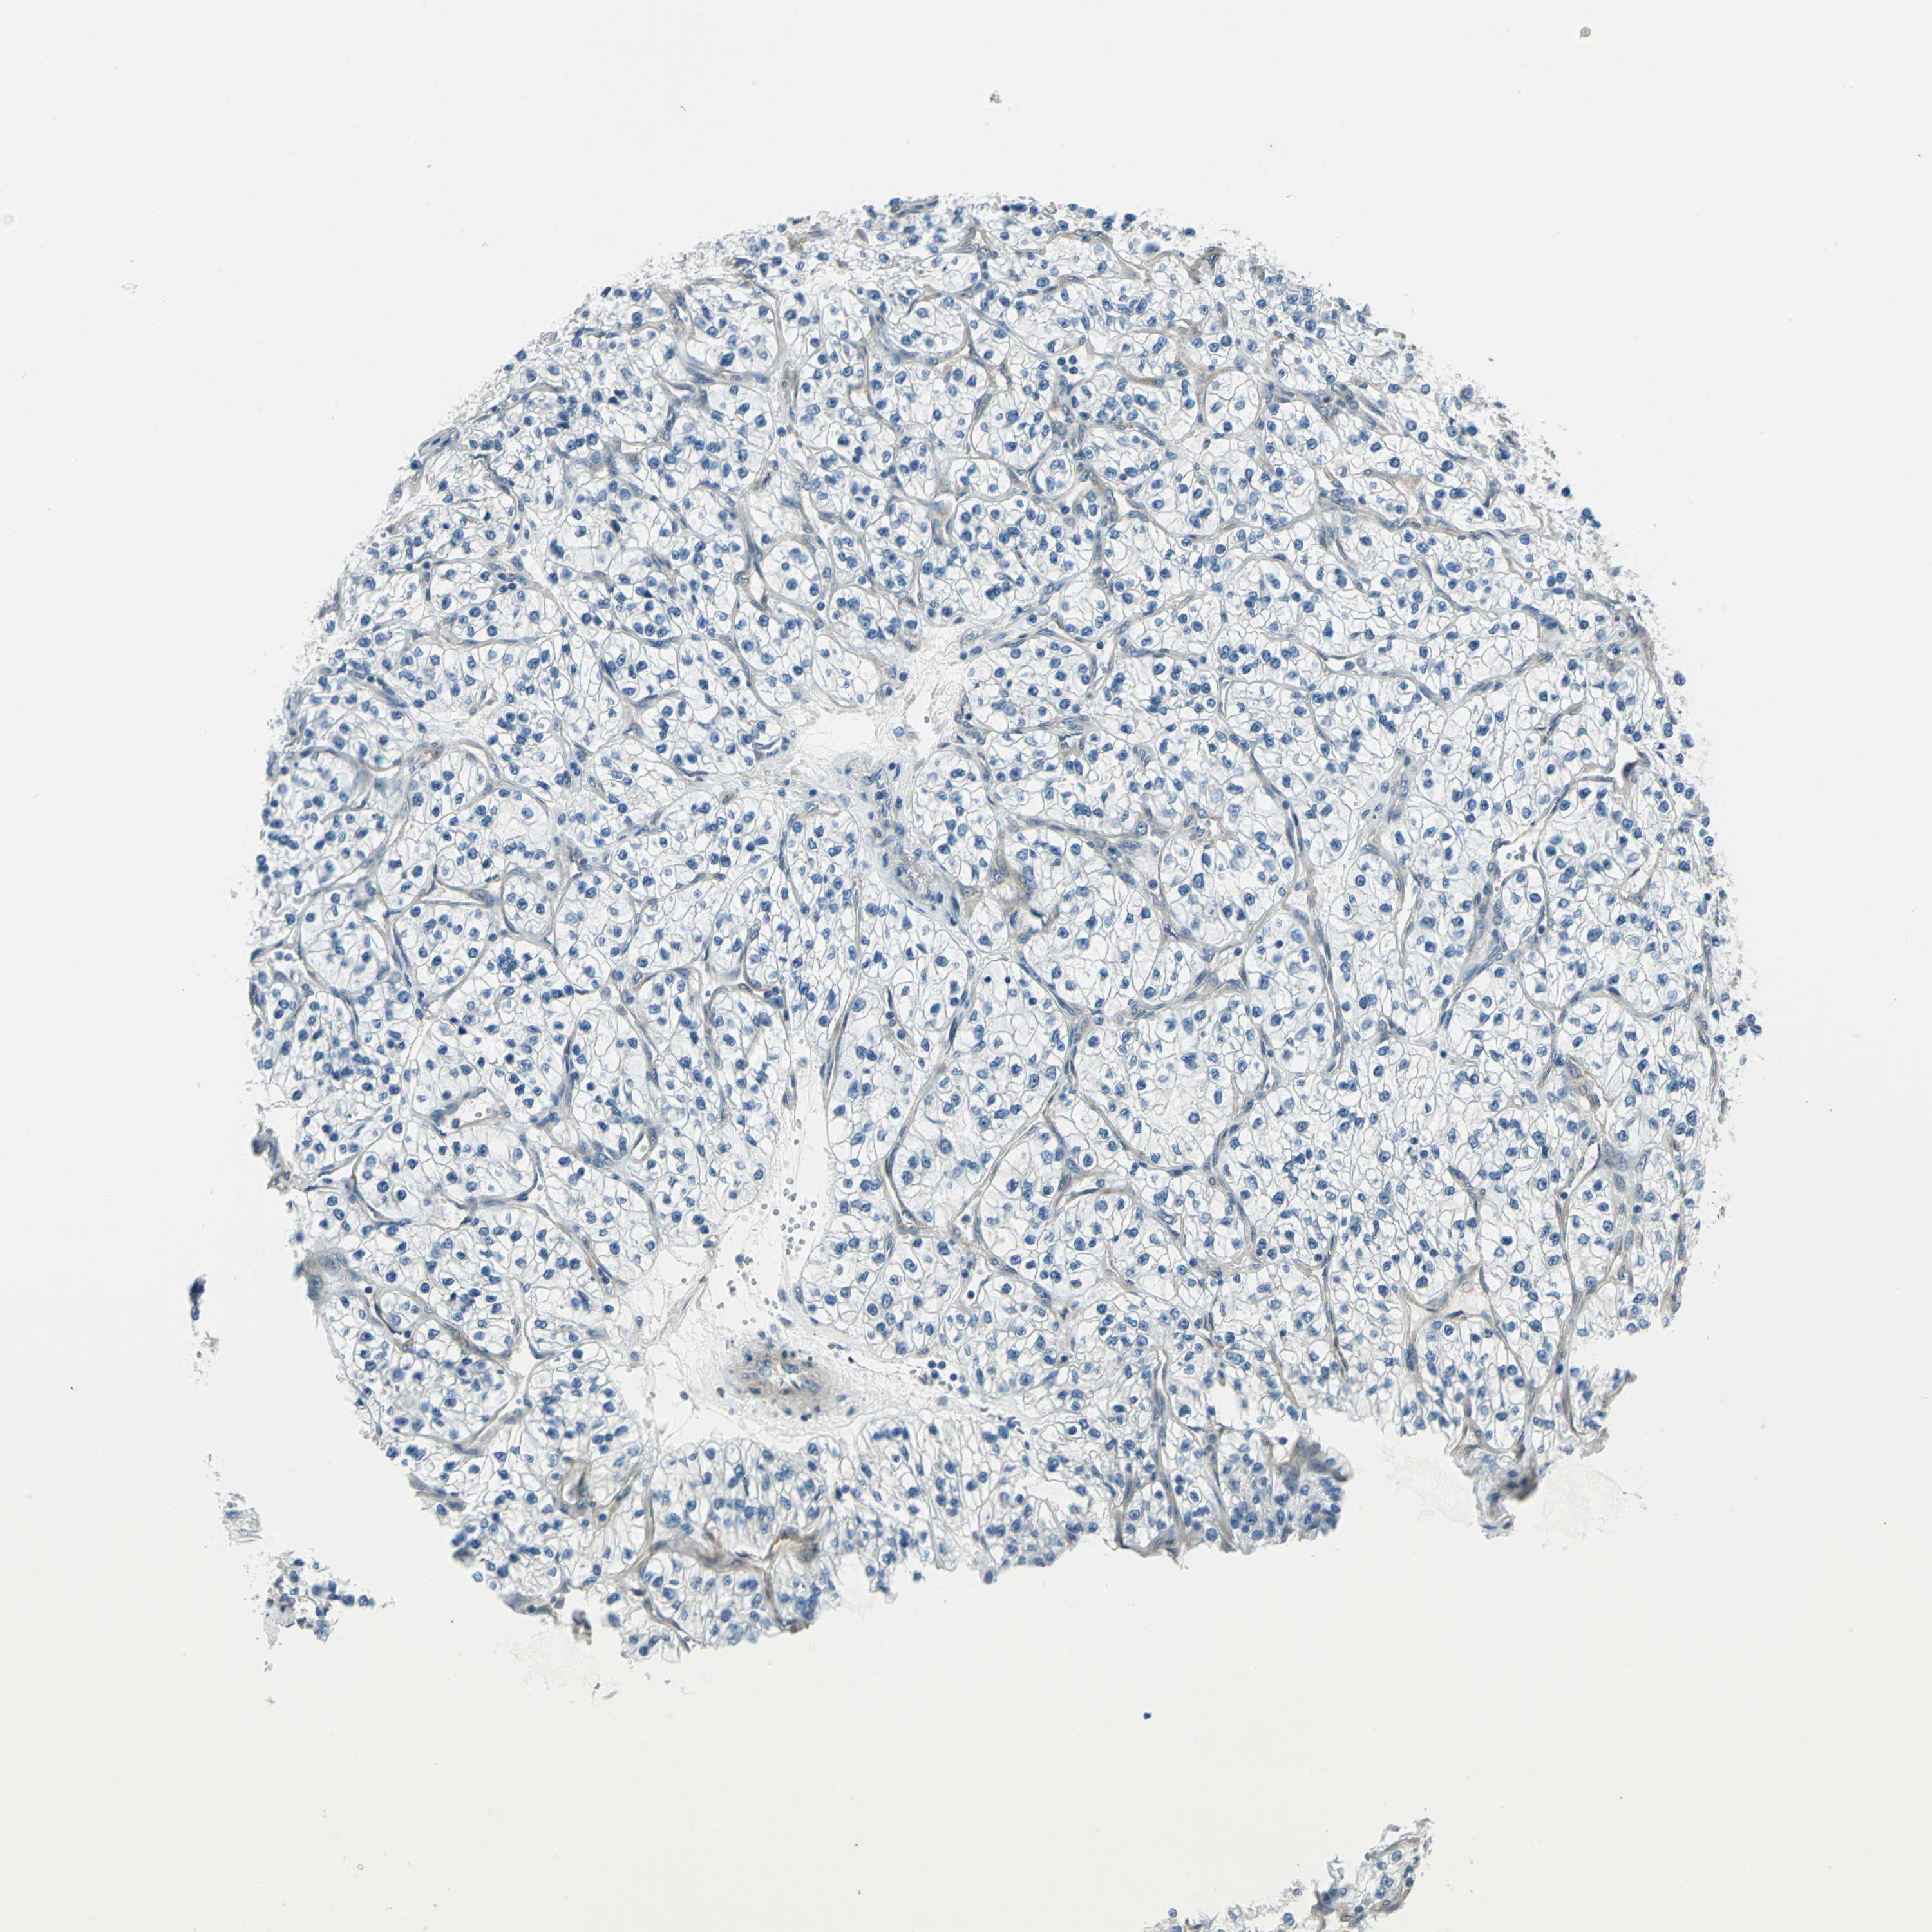

Renal cancer

Kidney renal papillary cell carcinoma